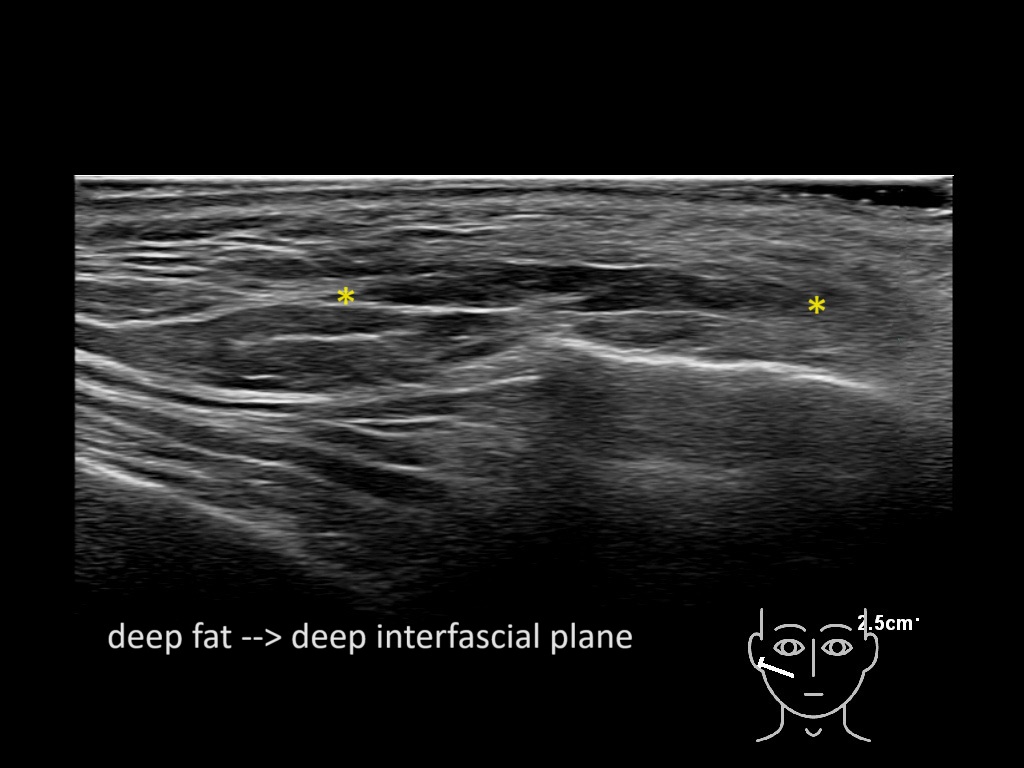

Filler behavior - Temple zygoma US

Study the first image to recognize the different layers. If you are sure about the layers, swipe to the second image to view the answer (if applicable).